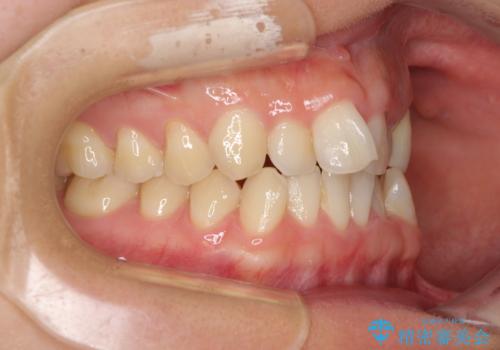

- 上下前歯のデコボコと銀歯のブリッジを気にして来院された患者様です。

装着されているブリッジを切断して矯正治療を行うことや、手間をかけずに早めに治療を終えたいとのことで、目立たないワイヤー装置による矯正治療を行うこととしました。